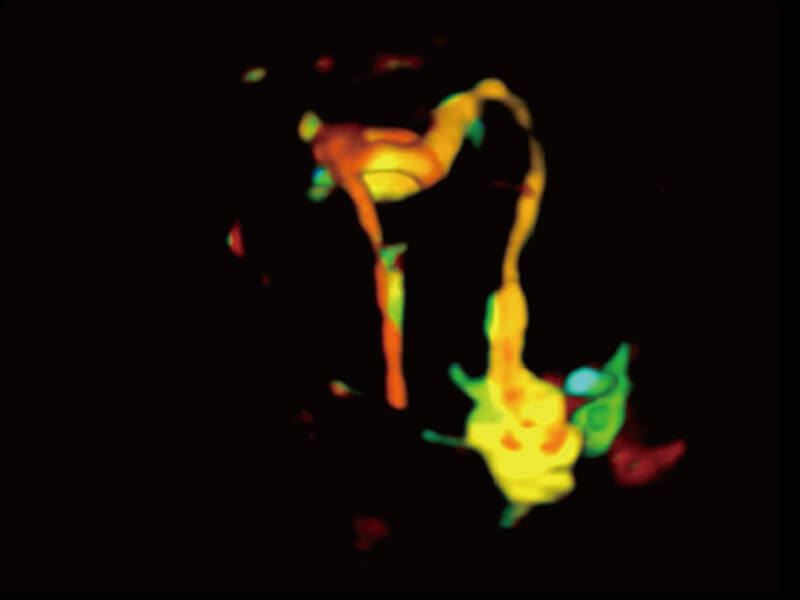

Micro F 显微血流成像 明察秋毫